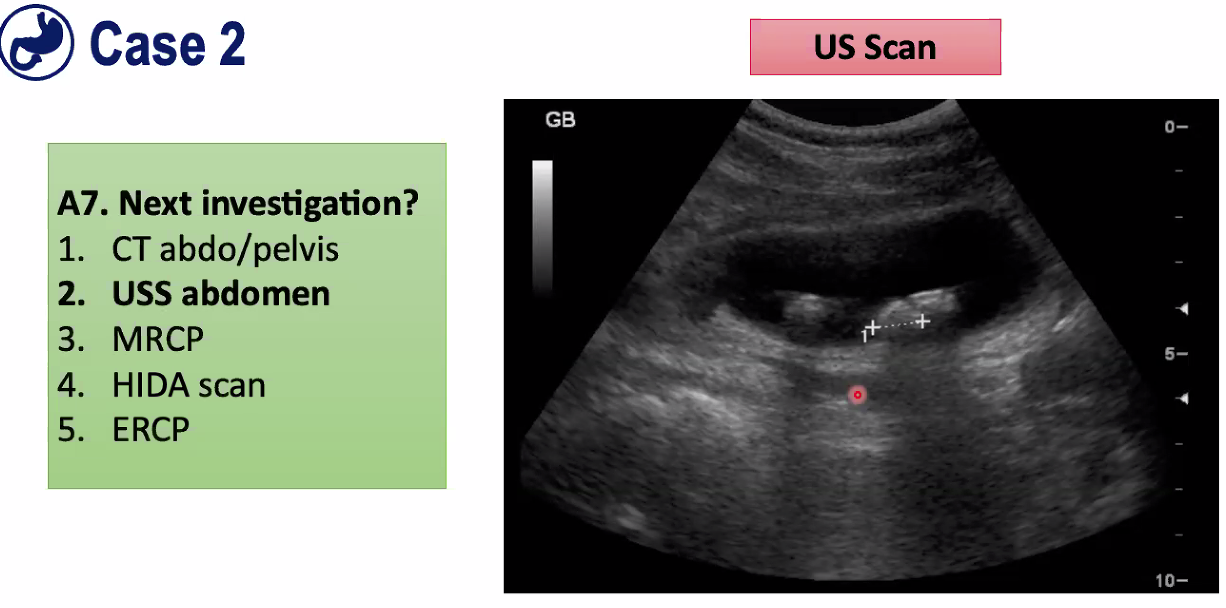

=USS abdomen

as have slightly raised bilirubin and a raised alkaline phosphatase, that means that something might be obstructing

1) as made diagnosis of gallstone pancreatitis, so first need to do is scan to see if they have actually got gall stones, if do then probs right

2) This also gives you a chance to see there is nothing in the bile duct itself. Might see obstruction of bile duct which would be inkeeping with poor liver function tests

This is gall bladder and can see gall stones inside as can see acoustic shadow below stones as ultrasonic waves are blocked by gall stone.